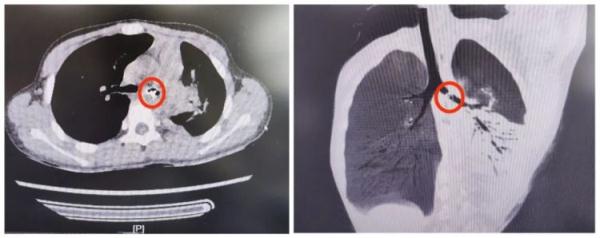

“医生、医生,孩子气管里呛进东西了 !”一位家长拿着当地医院的CT片焦急地冲进耳鼻喉科诊室。接诊医生赶紧询问病情,得知孩子将一文具零件不小心呛进了气管。

强强回家后不敢将实情告知父母。接下来的8天中,家长发现孩子总是时不时咳嗽,而且伴随发热,家长带着强强(化名) 就诊后,发现孩子胸部CT检查气管中竟有一异物,且伴随肺不张及肺炎,反复追问下强强才终于说了实话。 父母焦急万分,赶忙带孩子来到青岛妇女儿童医院耳鼻喉科就医。

接诊医生立即开通绿色通道,紧急完善相关手术评估后,进行手术。手术团队利用纤维支气管镜,发现有一个银色金属样物将左侧支气管完全阻塞,并且异物的部分边缘嵌入了气管壁黏膜。 手术团队精密操作,利用异物钳将异物完整取出。当异物取出后,患儿左侧支气管内涌出大量黄色脓性分泌物……